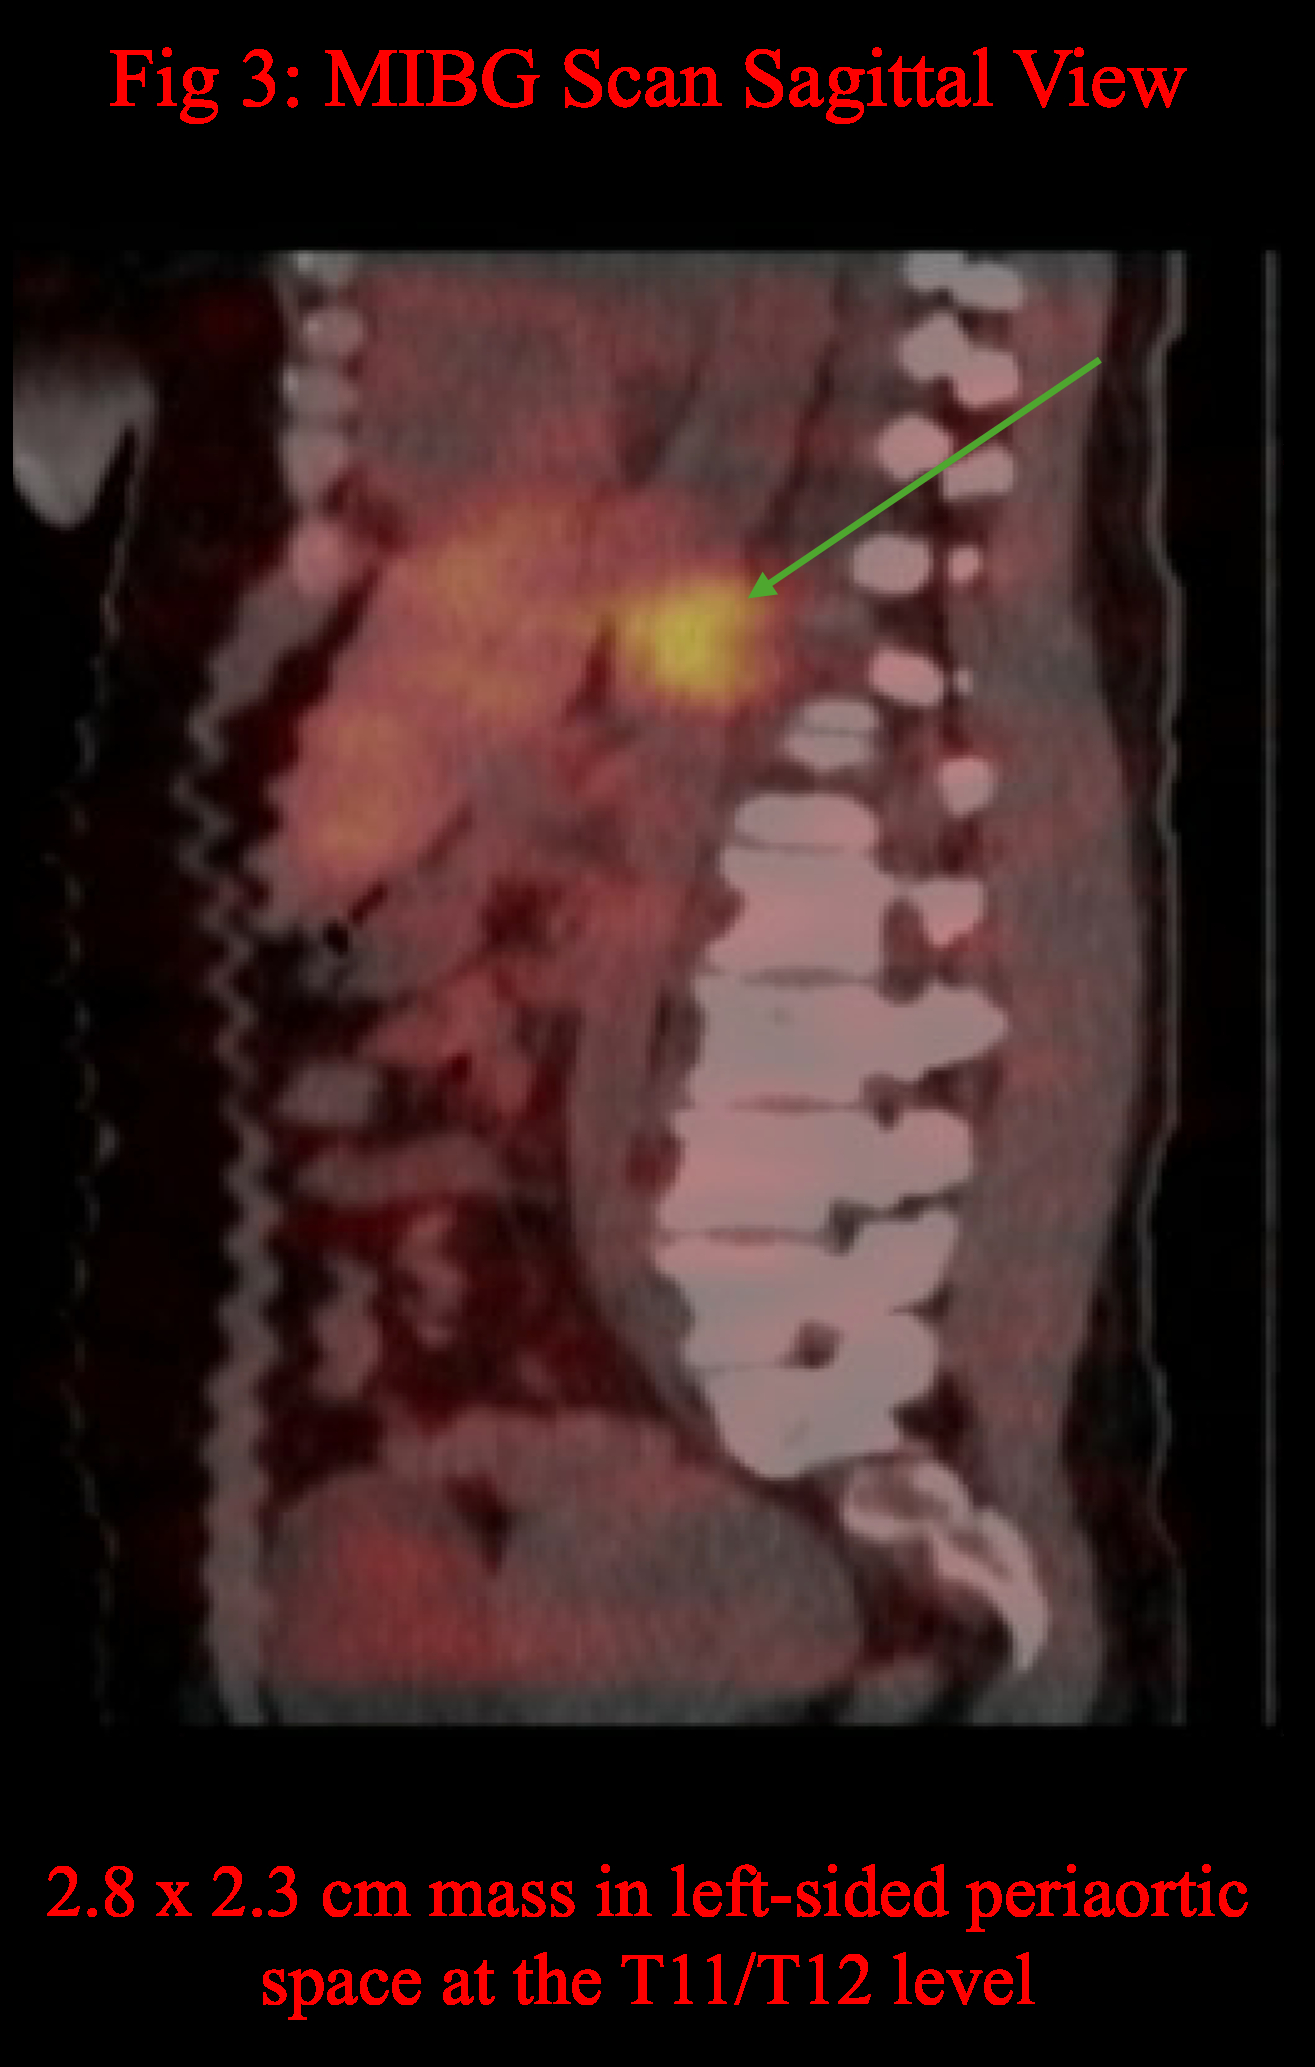

At the Rush Heart Center for Women, testing showed significantly elevated plasma and 24-hour urine normetanephrine levels. An MIBG scan with CT/SPECT identified a 2.8 × 2.3 cm mass near T11/T12, likely paraganglioma.

Current research links larger paragangliomas (>4 cm) with more symptoms, higher metanephrine levels, and increased metastatic risk, showing a correlation between tumor size and normetanephrine levels. However, in this patient, the tumor size remained stable on imaging while symptoms worsened, suggesting increasing metabolic activity. This case questions the reliability of tumor size as a marker of metabolic activity and highlights the possibility that slow-growing paragangliomas may become metabolically active before changes are visible on imaging. Further research is necessary to better understand this relationship and enhance patient care.